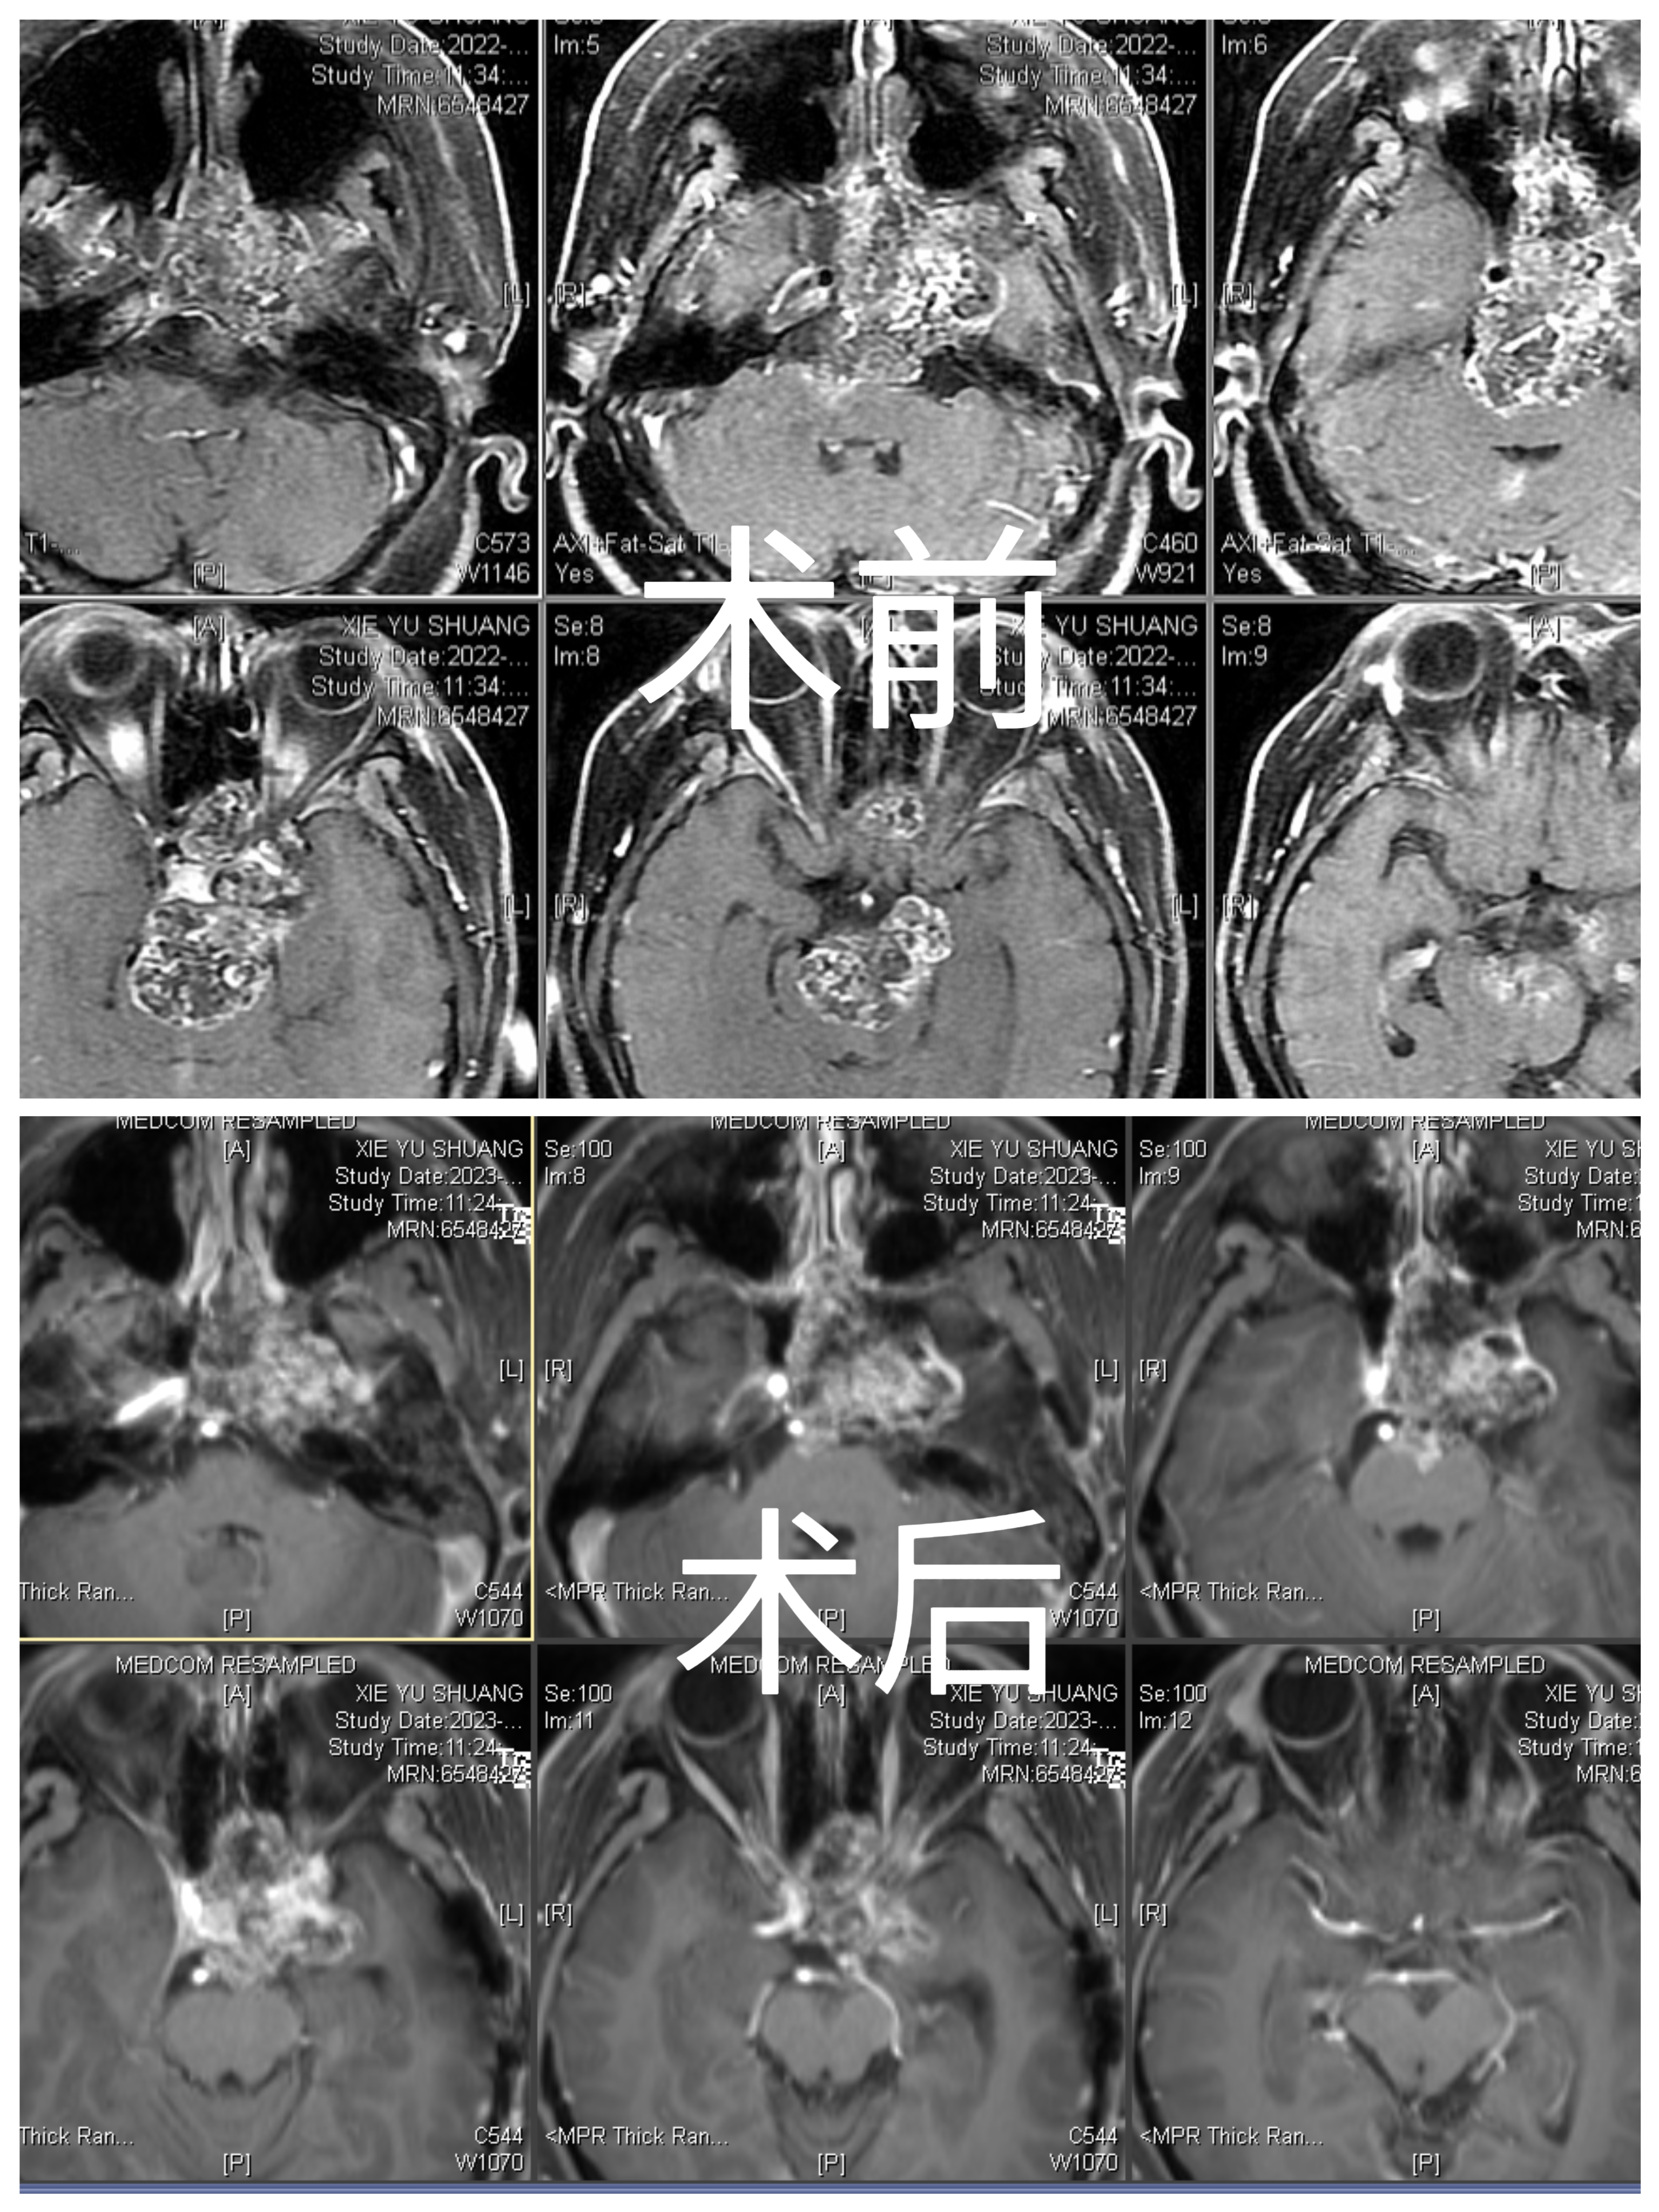

手术前

手术后